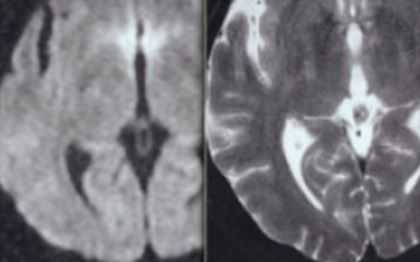

Диффузионно-взвешенные МРТ (DWI) наиболее чувствительны к цитотоксическому отеку ( в отличие от вазогенного, цитотоксический отек отражает переход жидкости из межклеточного пространство в клетки), которые ограничивает Броуновское движение вутриклеточной воды. Динамика ДВИ МРТ типична, примерно через сутки сигнал достигает максимума, но через 2 недели наступает псевдонормализация. Это отражает переход к фазе исхода, глиозным изменениям. На Т2-взвешенных МРТ головного мозга картина обратная, только к концу первых суток появляются изменения, постепенно нарастающие за счет отека, затем отграничения зоны инфаркта и, наконец, переход к исходу к концу месяца после начала ОНМК.

МРТ головного мозга. Диффузионно-взвешенные аксиальные МРТ. Острая стадия ОНМК в разных бассейнах кровоснабжения.

МРТ головного мозга. Динамика Т2-взвешенных МРТ, диффузионно-взвешенных (DWI) МРТ и МРТ карт диффузии (ADC) во времени.